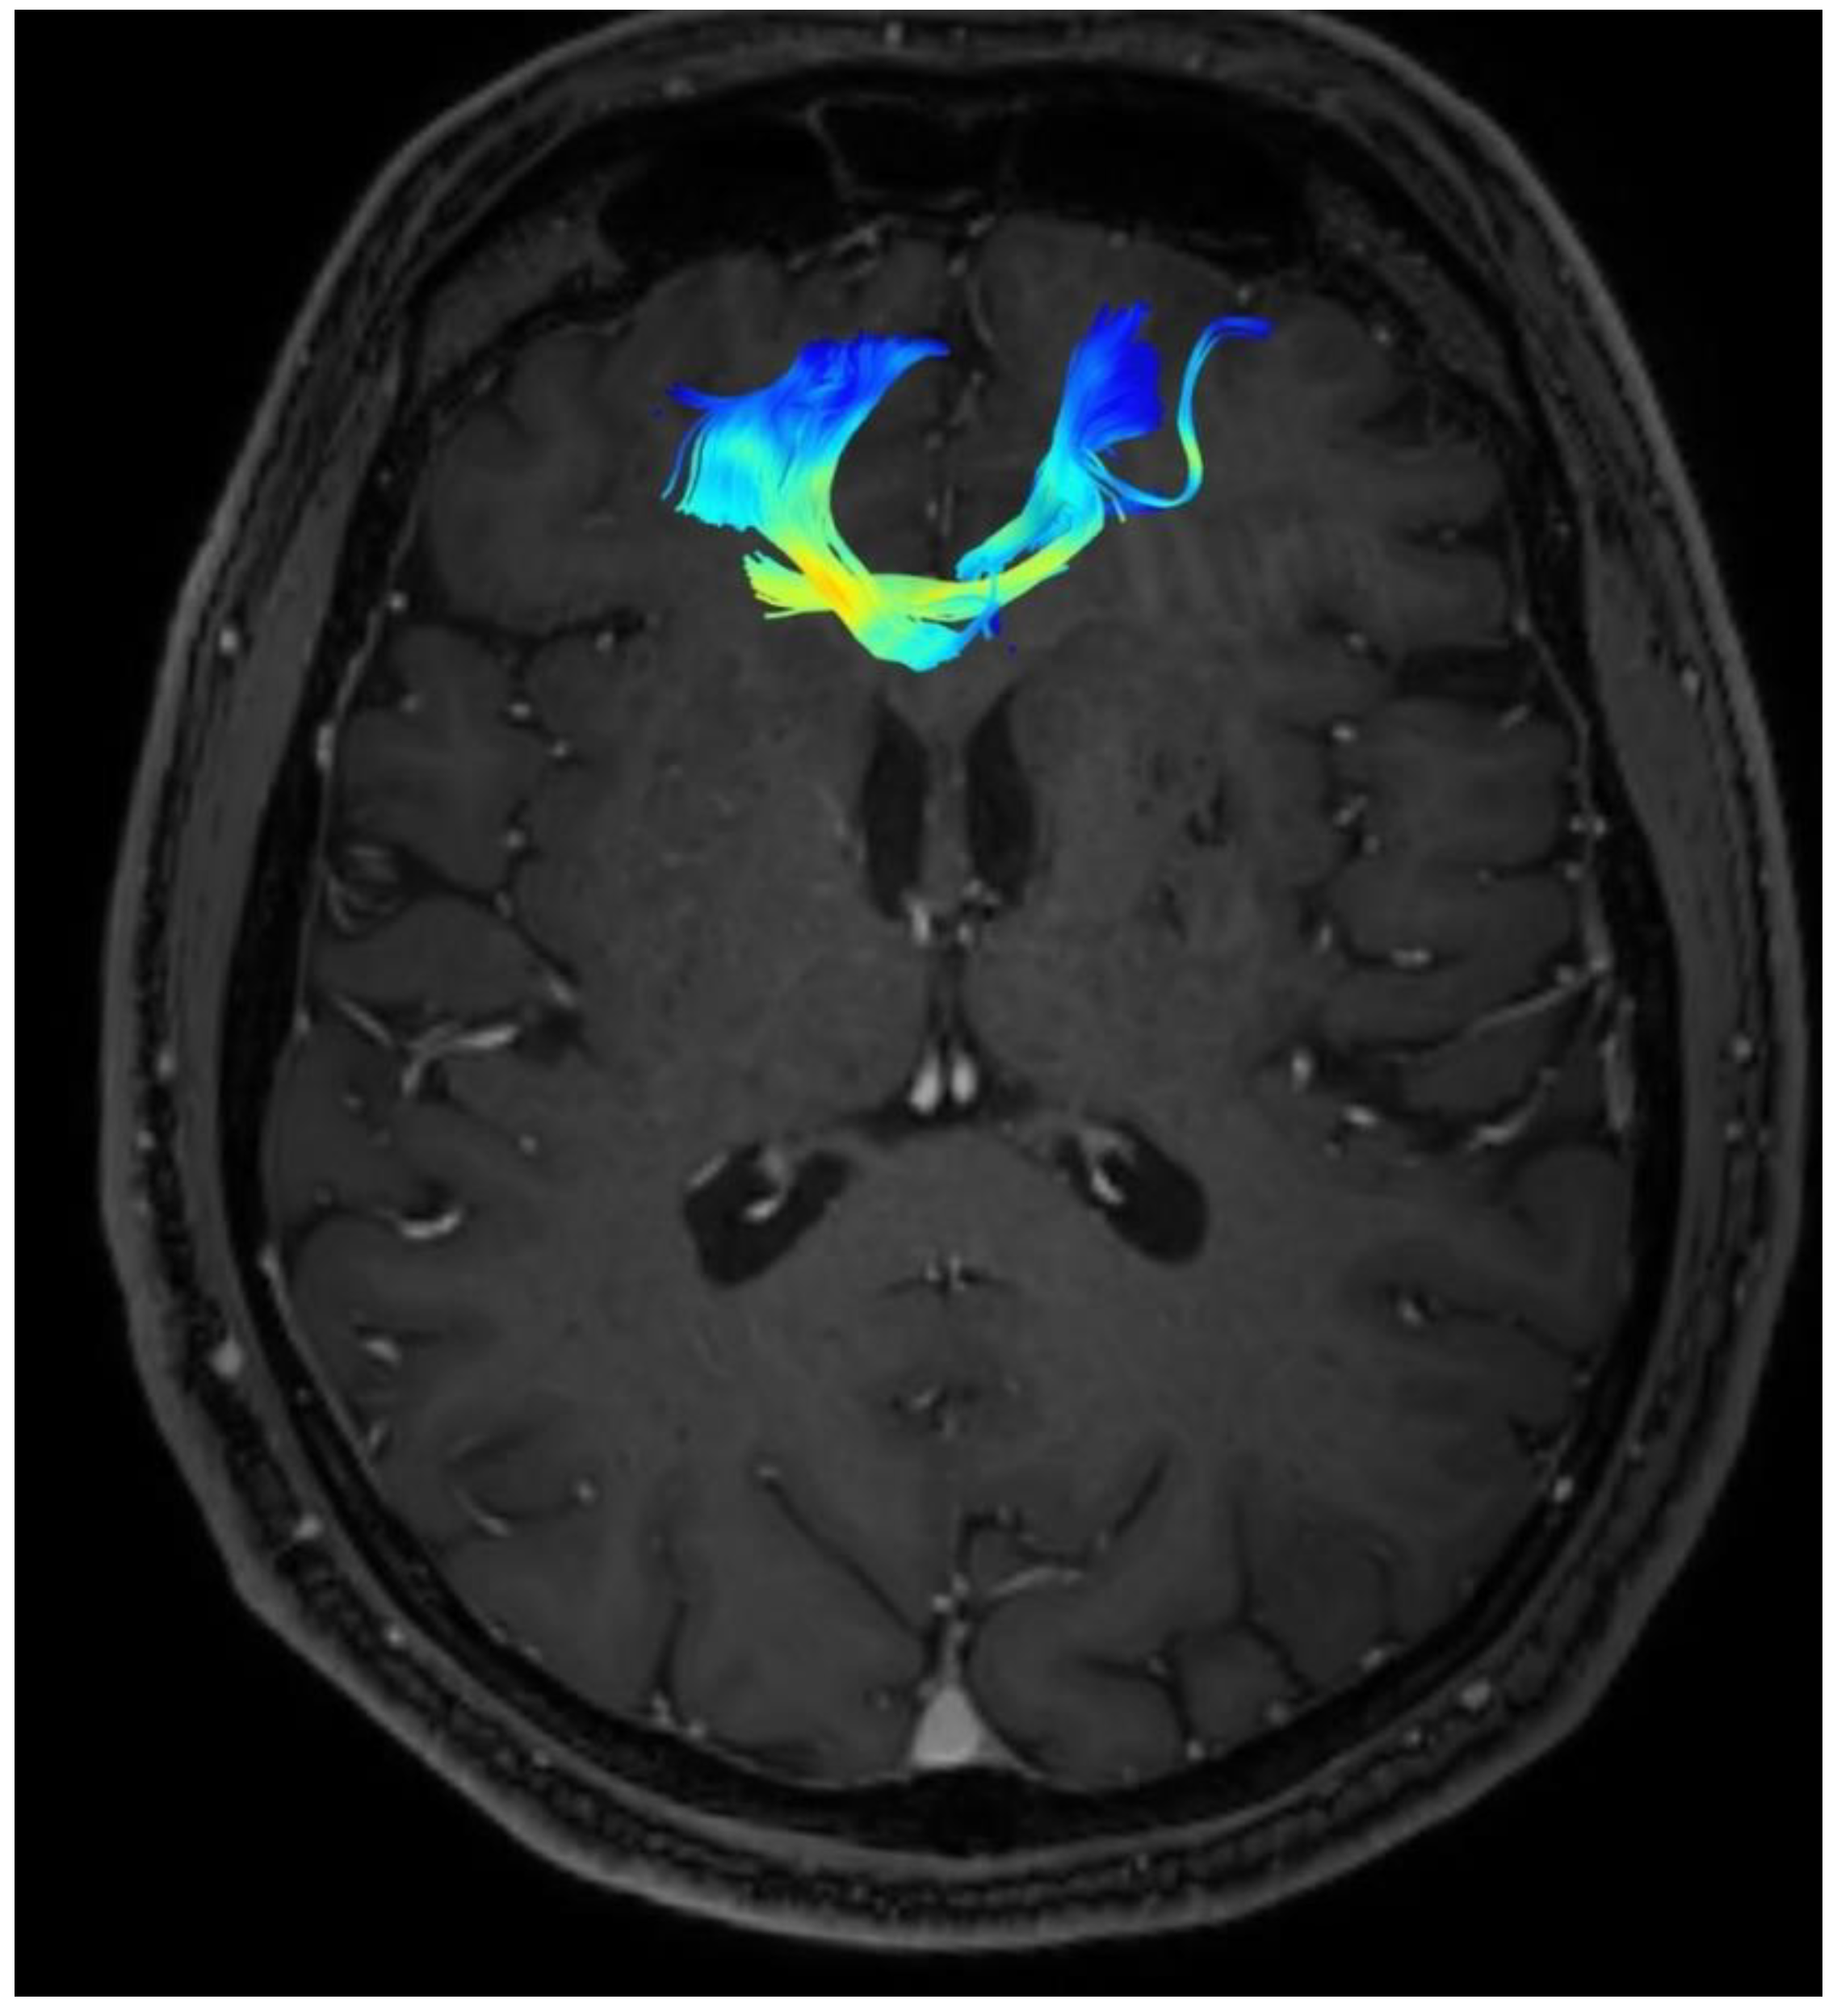

Changes in the anatomy of forceps minor before and after cingulotomy are presented in Figure 2 and Figure 3; moreover, arcuate fasciculus before and after cingulotomy is presented in Figure 4 and Figure 5.

Figure 3. Forceps minor after cingulotomy.